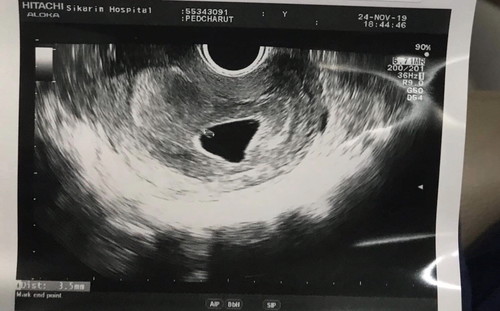

เลือดออกเป็นสีน้ำตาลไปหาหมอ หมอบอกอาจจะท้องลม หรือน้องหยุดการเจริญเติบโตแล้ว ให้รอซาวอีก1-2สัปดาห์ ตอนนี้เลือดก็ยังไม่หยุด (แต่เปนสีน้ำตาลไม่ปวดท้อง ไหลน้อย) หมอบอกแค่ให้รอ แต่ในถุงตั้งครรภ์ไม่ได้ว่างป่าว มีจุดขาวๆอยู่ในนั้น แต่ไมไ่ด้ยินเสียงหัวใจ ???

ท้องแรก